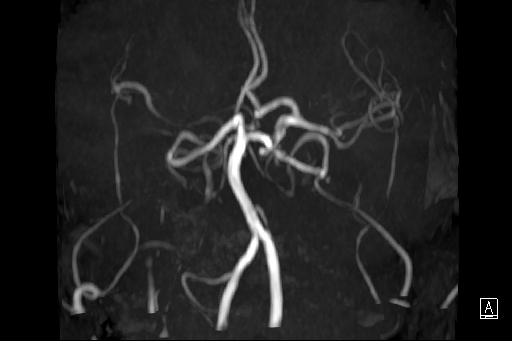

MRI revealed invisible of bilateral ICA, angiography showed bilateral CCA total occlusion with bridge collaterals.ABI showed severe decreased over both sides

Carotid angiography showed bilateral CCA occlusion with bridge collaterals from vertebral and subclavian artery. Patient refused surgical endarterectomy. Lower limbs angiography revealed right SFA CTO, left SFA distal stenosis.We tried endovascular treatment for left CCA occlusion first but failed.